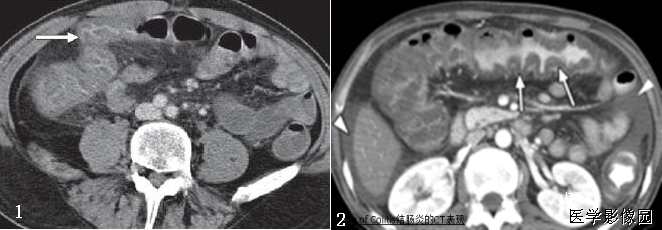

下边两幅图更典型:

图1:非何杰金淋巴瘤患者口服造影剂后增强CT横断面。显示2个巨大系膜淋巴肿物(2个面包-带尾箭头),包绕中心系膜和增强的血管。注意增强的小肠位于周边,腹膜后淋巴结显著增生-箭头)。

图2:患者6个月前曾行左肾移植发现PTLD,血管和口服造影剂横断CT显示三明治征——系膜淋巴肿物(实心带尾箭头),靠近右肾(箭头),有腹膜淋巴结肿大(空心带尾箭头)。